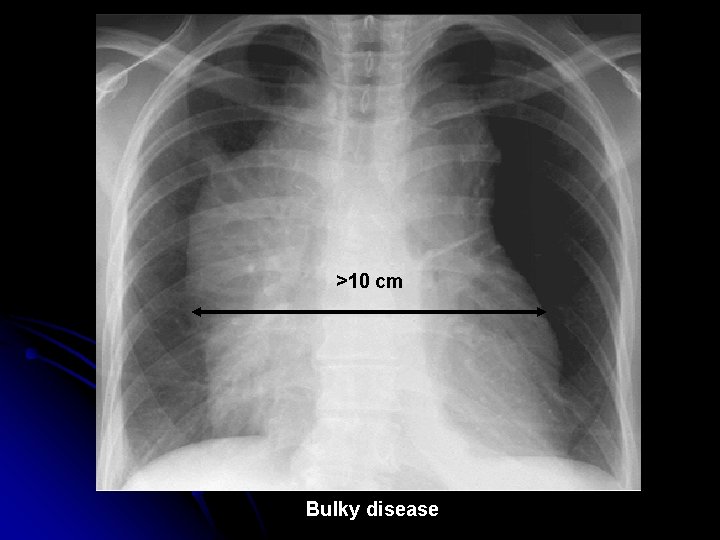

Constitutional symptoms ( B symptoms ) l Night sweats, l sustained fever > 38 degree celsius, l loss of weight >10% of body weight in 6 mo l Fever sometimes cyclical (‘Pel-Ebstein fever’) l Pain at the site of disease after drinking alcohol l Pallor l Pruritis l Symptoms of Bulky (>10 cm) disease l

>10 cm Bulky disease

Treatment - Guidelines l Indications for RT: l Stage I disease l Stage II disease with 3 or lesser areas involved l For Bulky disease l For pressure problems l Indications for CT l All with B symptoms l Stage II disease with >3 areas involved l Stage III and IV disease

Treatment l Stage IA , Stage IIA with 3 or < 3 areas involved: Radiotherapy l Stage IB, Stage II A with > 3 areas , Stage IIB: Chemotherapy every 3 -4 weeks, 6 -8 cycles; either alone, or in combination with radiotherapy l Stage III & IV : Chemotherapy + Radiotherapy ( for bulky disease or palliation of symptoms)